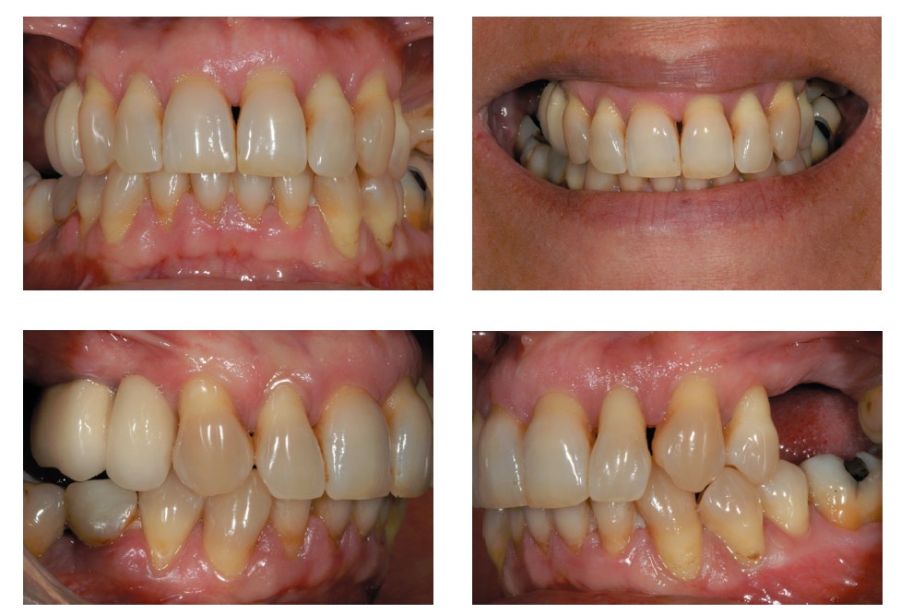

Presentamos el caso de una paciente femenina de 56 años de edad que acude a la consulta demandando un tratamiento con implantes dentales para reponer los dientes ausentes en ambos sectores posteriores maxilares. En ambos cuadrantes superiores, los molares se perdieron hace varios años. La paciente no se ha realizado la reposición de los mismos hasta ahora, ya que en otros centros consultados la propuesta terapéutica fue la de realizar injertos y regeneración ósea para poder ganar volumen óseo suficiente antes de colocar los implantes. La paciente busca otras alternativas menos invasivas y por ello acude a la visita. En las imágenes intraorales se observa la falta de los molares en los sectores posteriores maxilares con excepción del 27, que actualmente tiene un compromiso periodontal importante (Figuras 1-4). El resto de dientes también se encuentran afectados por una enfermedad periodontal avanzada con pérdida ósea horizontal (Figura 5).

Como primer paso, se realiza un escaneado intraoral de la paciente, para poder generar un encerado virtual con las piezas que queremos rehabilitar con implantes (Figuras 6-8). Esto nos permite planificar con claridad el caso y desde el modelo tridimensional, generar los provisionales y las guías quirúrgicas basadas en la posición protésica, que desde el flujo digital pueden imprimirse (Figuras 9-14). Desde el encerado podemos además generar otras guías, en este caso radiológicas, con las que realizar el Cone-Beam Computed Tomography (CBCT) de planificación. Con esta información tenemos en el mismo estudio radiológico la fusión de nuestra planificación quirúrgica y la posición real de la prótesis adaptada a la oclusión, muy útil para generar una planificación que contempla todos los parámetros. En este caso, se planifican implantes cortos de 6,5 mm en el primer cuadrante, de morfología Core-Xâ, para lograr una correcta estabilidad primaria en un tipo óseo IV como vemos en el corte seccional (Figuras 15 y 16). En el segundo cuadrante, con similares características, planificamos implantes de 6,5 y 5,5 mm de longitud (Figuras 17 y 18).